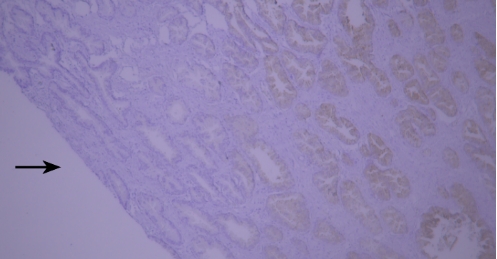

(V) Tissue Drying IssueTypical example:

TIMP-1 staining of paraffin-embedded human prostate tissue sections showed false negatives due to tissue drying (indicated by black arrows).

Recommendation for Resolution: Using a buffer supplemented with Tween-20 can effectively prevent section drying.